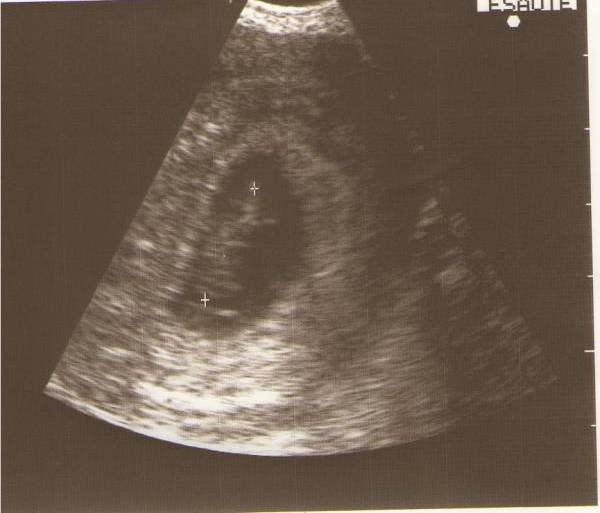

Szencse, köszönöm szépen a képet! Nagyon édes! Jajj mikor lesz már nekem is ekkora

Irigykedek ám

Főleg ha fiús pocakod van

Bár tudom te nem azt akarsz, ugyhogy drukkolok, hogy mégiscsak kislány legyen! De ha nekem lány neked fiú, majd cserélünk